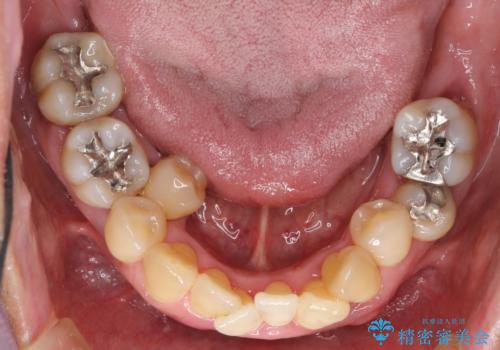

インプラント治療を併用した全顎歯周病治療

- 「仕事のリタイヤに目処がつき、今後は自分の健康にお金をかけたい。しっかりと食事ができる口腔内環境にしてほしい。」と全体的な治療を希望され来院されました。

全体的に重度の歯周病が認められ、抜歯が必要な部位はインプラント治療を、残すことのできる歯には再生治療を含めた歯周病治療を行い全体的な治療を進めてきます。